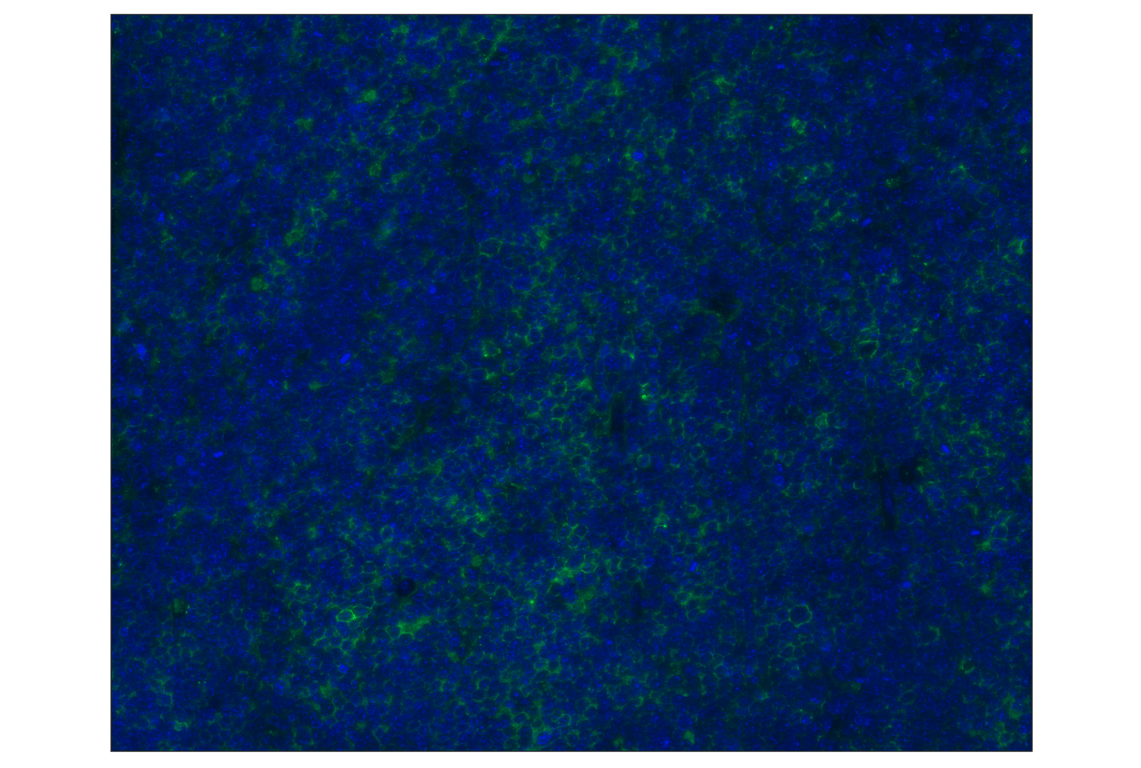

PD-L1 (D5V3B) Rabbit Monoclonal Antibody (Alexa Fluor® 488 Conjugate) #20490

This Cell Signaling Technology® antibody is conjugated to Alexa Fluor® 488 fluorescent dye under optimal conditions. This antibody conjugate is expected to exhibit the same species cross-reactivity as the unconjugated PD-L1 (D5V3B) Rabbit mAb #64988.

Immunohistochemistry (Paraffin) 1:100 - 1:400

PD-L1 (D5V3B) Rabbit Monoclonal Antibody (Alexa Fluor® 488 Conjugate) recognizes endogenous levels of total mouse PD-L1 protein. Non-specific staining of keratinized epithelium has been observed.

Mouse